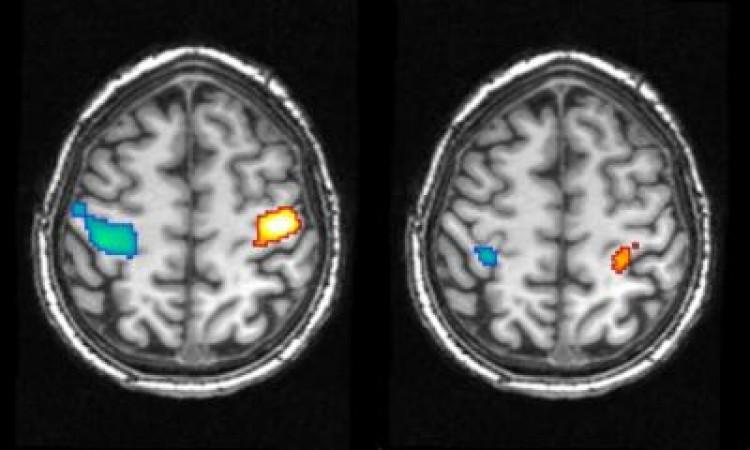

The researchers discovered that brain activity is very similar whether dreaming, visualizing, or actually carrying out a specific action, although brain activity was about half as strong during sleep.

Six lucid dreamers slept in an functional magnetic resonance imaging (fMRI) machine to measure blood flow within their brains. They signaled with their eyes when they were about to start dreaming, and then purposely dreamed that they were clenching their fists, starting with the right fist for the first 10 seconds of their dream and then the left fist.

Further brain scans were taken while the same people clenched their fists when awake, and again while they only imagined clenching their fists.